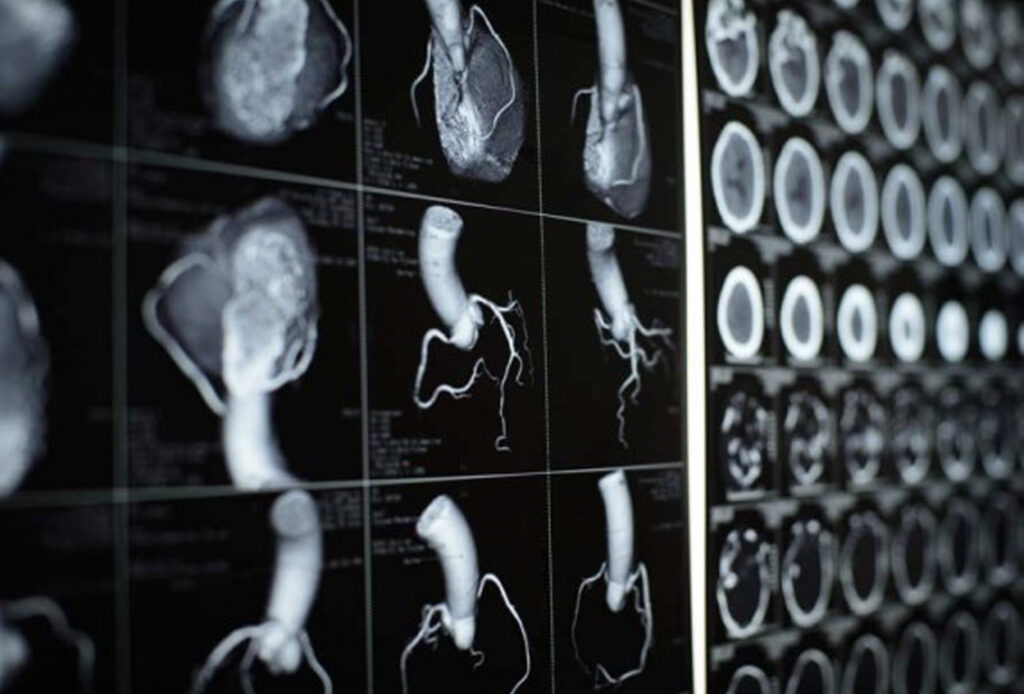

CT scan jantung adalah prosedur pemindaian yang menggunakan sinar X-ray dari berbagai sudut untuk mendapatkan gambar jantung, pembuluh darah, dan struktur di sekitarnya secara tiga dimensi (3D) berkualitas tinggi.

CT scan jantung atau CT cardiac adalah suatu jenis pemeriksaan pencitraan medis menggunakan sinar-X dan teknologi tomografi komputer untuk menghasilkan gambar 3D dari jantung, pembuluh darah, serta struktur di sekitarnya.

Evaluasi dari hasil CT scan jantung umumnya melibatkan analisis struktur dan bentuk jantung (morfologi), serta pemeriksaan CT angiogram koronaria untuk melihat keadaan pembuluh darah arteri koroner yang menyuplai darah ke jantung. Selain itu, terdapat metode pemeriksaan lainnya yaitu CT calcium score atau disebut juga sebagai coronary calcium scan, yang dilakukan untuk mengukur calcium score pada pembuluh darah arteri koroner untuk mengidentifikasi tingkat kalsifikasi yang dapat menjadi tanda risiko serangan jantung.